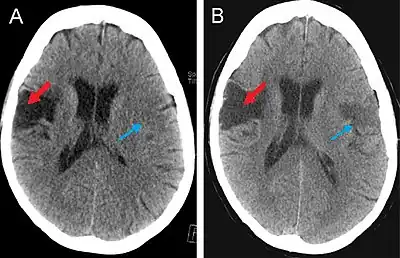

CT Scan

This computer-tomography type of imaging is one of the most used in any clinical environment and although it can detect some of the brain areas affected by a stroke or a trauma it does not provide the same acuity as the magnetic resonance imaging. CT scans can also reveal, in patients with the syndrome, the bilateral cortical infarcts located in the posterior frontal region involving the opercular areas.[3]